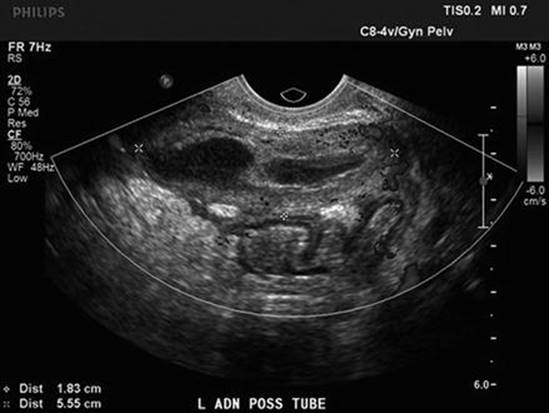

TOA

Tubo-ovarian abscesses are usually diagnosed by imaging, in a patient with the symptoms and physical exam findings of PID. A patient with TOA may also have a palpable pelvic mass or adnexal fullness on physical exam. Transvaginal ultrasound and/or computed tomography (CT) scan is often obtained for the diagnosis of TOA. The sensitivity and specificity of transvaginal ultrasound for tubo-ovarian abscesses are greater than 90 % [18]. TOAs will appear as complex, loculated cystic masses with thickened irregular walls; internal debris may be seen (Fig. 6.3).

Fig. 6.3

Ultrasound image of pyosalpinx (Reprinted from Chappell and Wiesenfeld [19], with permission)